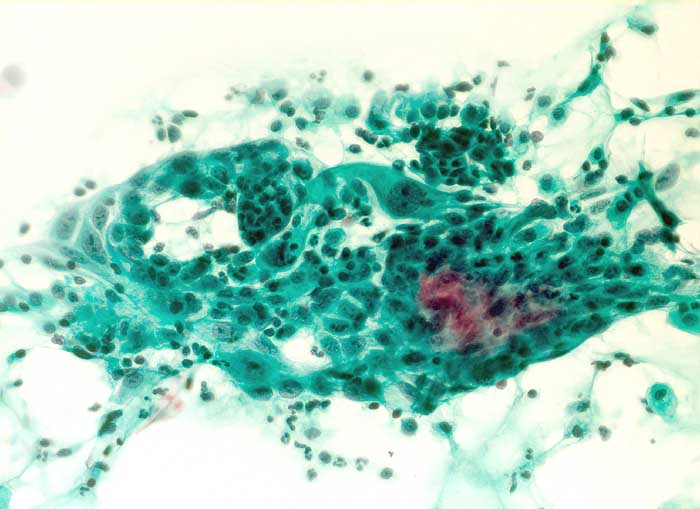

Nicht klassifizierbare Zylinderepithelien

Portioabstrich: Polygonale und zylindrische Zellen mit vergrösserten vesikulären Kernen. Im Hintergrund neutrophile Granulozyten.

Zytologische Diagnose: Regenerationsepithel, Endometriumverbände und deziduale Zellen. Keine Malignitätszeichen. Befund vereinbar mit Schwangerschaft.